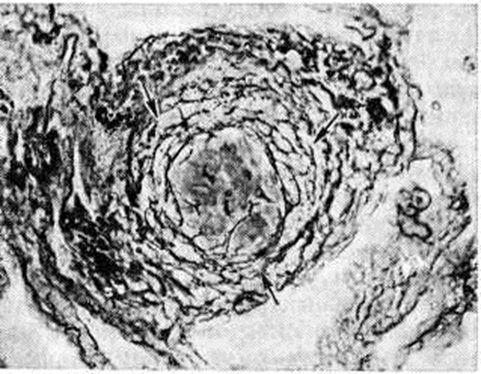

Рис. 1.

Микропрепарат лёгкого при антракосиликозе: концентрическое расположение коллагеновых и аргентофильных волокон в фиброзном узелке (указано стрелками); импрегнация по Тибор-Паппу; × 300.

При силикозе и антракосиликозе в лёгких и регионарных лимфатических, узлах присутствуют типичные клеточнофиброзные и фиброзные узелки с концентрическим расположением коллагеновых и аргентофильных волокон (рисунок 1).